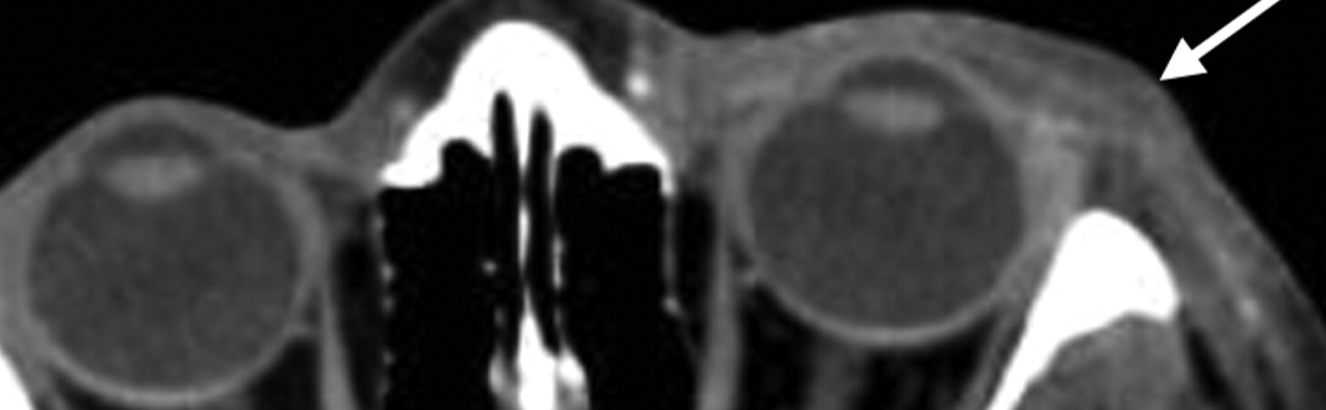

Describe the Arterial Supply of the Eyelids.

eyelids are richly vascularized

Main supply: Vascular arcades formed by the medial & lateral palpebral branches of the ophthalmic artery

Upper lid: 2 arcades

Lower lid: 1 arcade

Additional supply: Branches from the infraorbital, facial, transverse facial, and superficial temporal arteries